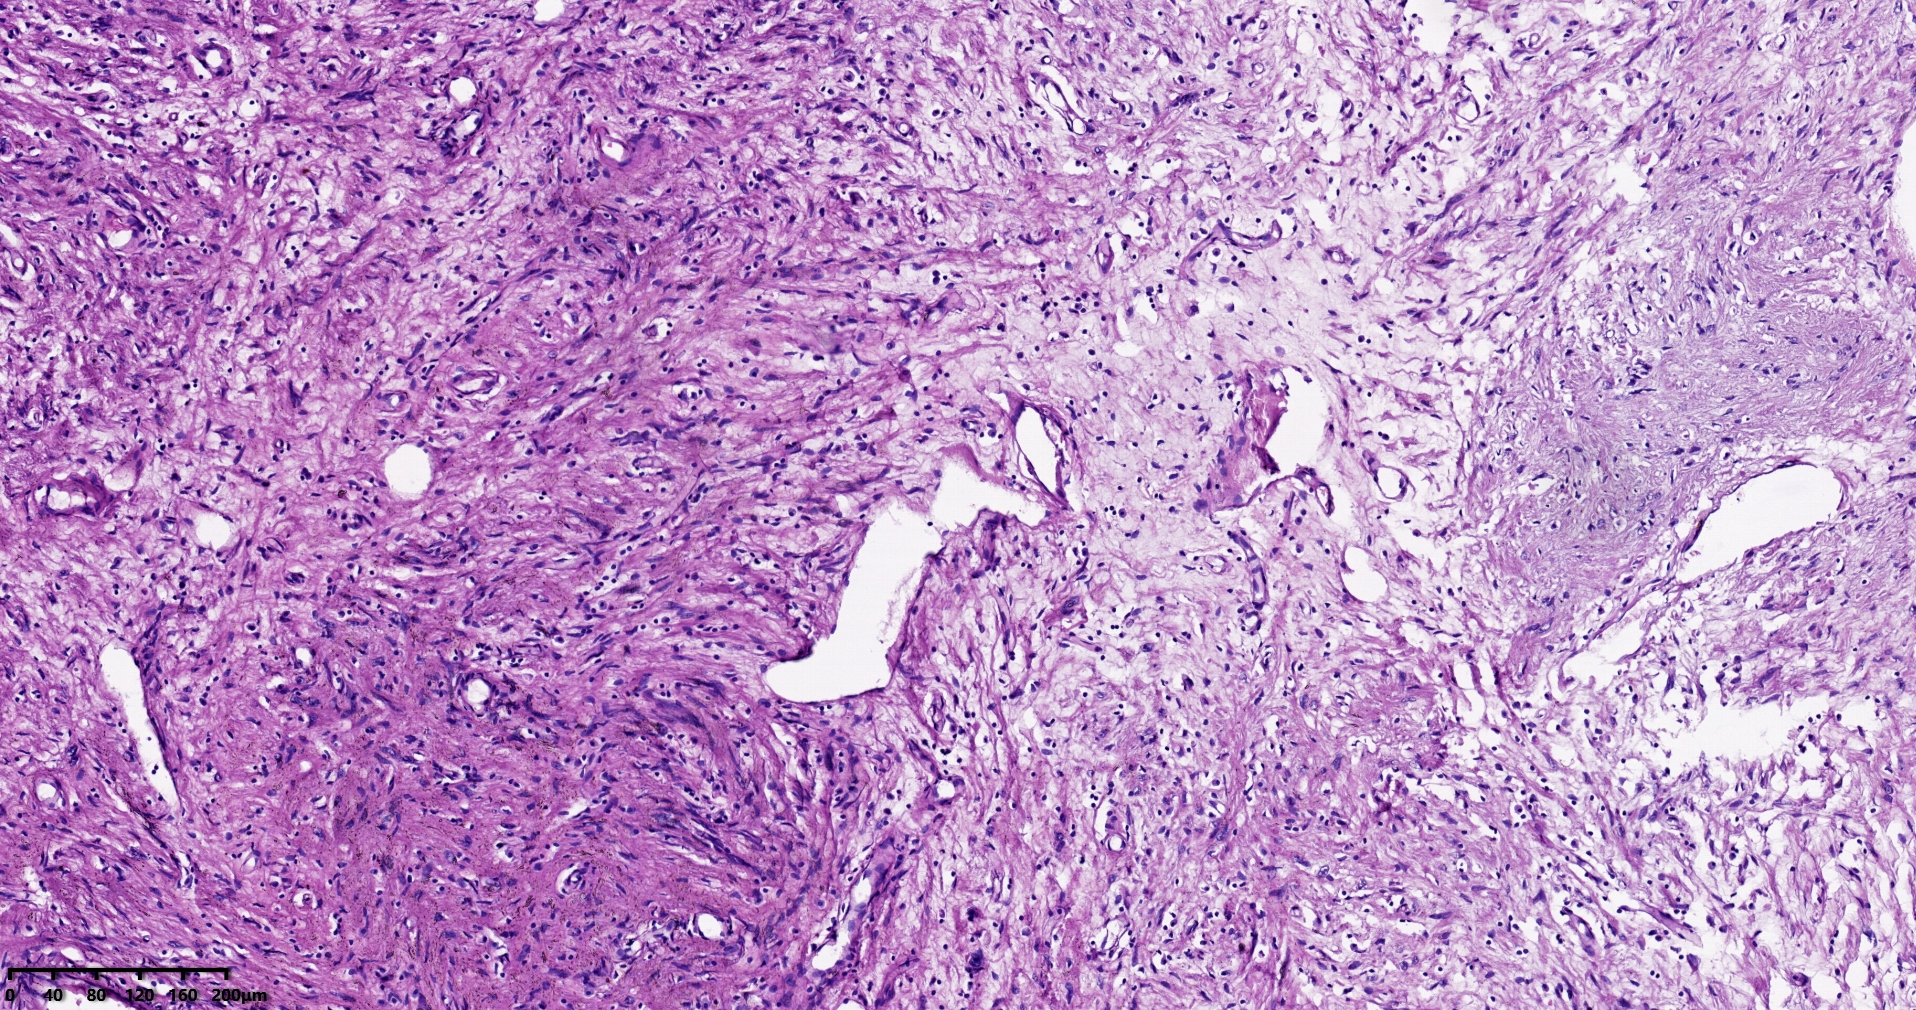

结肠肝曲息肉状肿物,平滑肌瘤?胃肠道间质瘤?炎性纤维性息肉?

性别

男

年龄

56岁

临床诊断

结肠肝曲息肉

一般病史

不详

标本名称

大体所见

灰红色椭圆形息肉一个,直径2.5cm,蒂长0.5cm,切面灰白灰红色,质中。

请路过的老师指教。

考虑间质瘤?

就HE形态而言,间质瘤的可能性要大一些,建议做免疫组化协助鉴别。